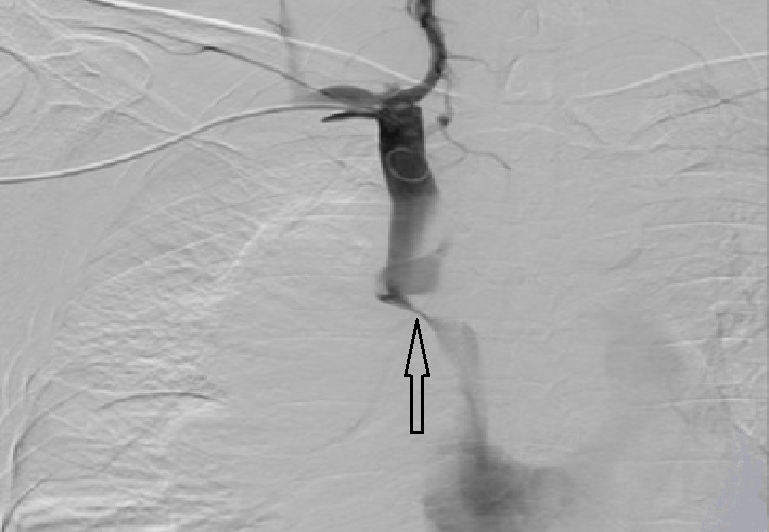

Критический стеноз верхней полой вены

• По результатам каваграфии можно оценить состояние вен исследуемой области, наличие сужений, расширений, тромбы в венах. Кроме того, при каваграфии определяется сдавление вен опухолями средостения, органов забрюшинного пространства.